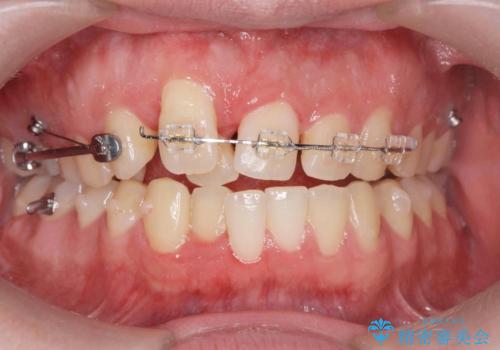

正中過剰埋伏歯で生じた前歯の審美障害 矯正治療での改善

- 前歯の見た目に悩まれて来院されました。

当初他院では、抜歯を行いセラミックブリッジを提案されていましたが、他の方法はないかと総合歯科治療を行う当院へと相談来院されました。

「時間がかかっても良いので、できれば歯を抜かずに矯正治療で治したい。」という強い希望があったので、矯正治療で歯並び・審美性の改善を計画します。

見た目、噛み合わせが大きく改善し、大変喜んでいただくことができました。